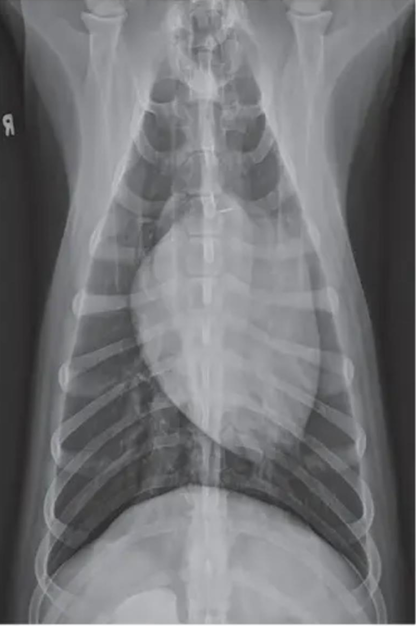

![]() | Pleural effusion - 물이 차서 심장이 안 보이고 폐가 들려 있고 끝이 뭉툭. - tracheal elevation - 흉수 뽑고 다시 찍어봐야 함. |